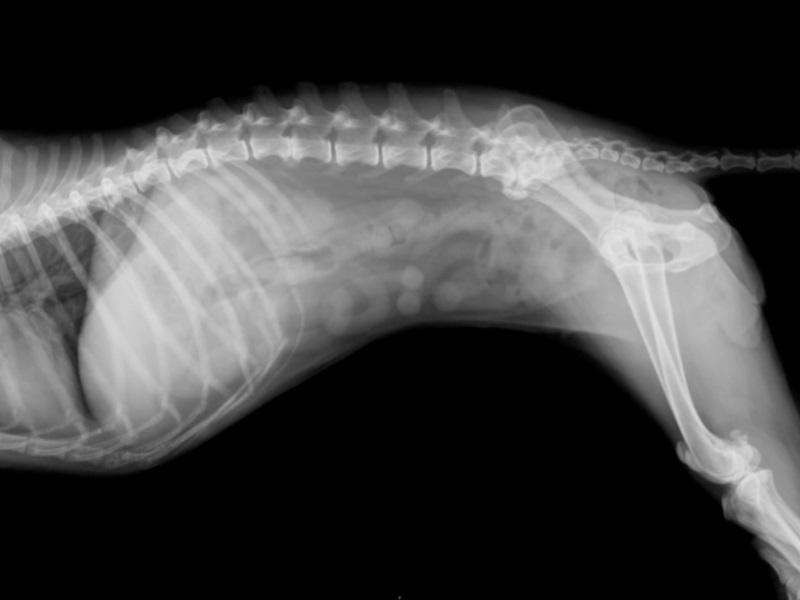

Для диагностики заболеваний позвоночника применяются рентгенографическое исследование со использованием специального рентген-контрастного вещества.

Необходимо также рентген позвоночника собаки, что позволит визуализировать происходящие дегенеративные процессы.

Рентген дает возможность увидеть расположение остеофитов, заподозрить сужения канала спинного мозга, наличие минеральных структур и грыж.

Контрастная рентгенография – миелограмма, проводиться с целью детального исследования и дифференциации. Данная методика позволяет выявить место нахождения грыжи более точно, оценить состояние повреждений спинного мозга. В современных ветеринарных лечебницах используется магнитно-резонансная томография.